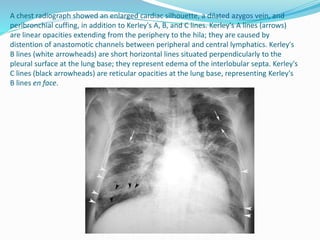

 Kerley A lines-These are longer (at least 2cm and up to 6cm) unbranching

lines coursing diagonally from the hila out to the periphery of the lungs. They

are caused by distension of anastomotic channels between peripheral and

central lymphatics of the lungs. Kerley A lines are less commonly seen than

Kerley B lines. Kerley A lines are never seen without Kerley B or C lines .

 Kerley B lines

 Kerley B linesThese are short parallel lines at the lung periphery. These lines

represent interlobular septa, which are usually less than 1 cm in length and

parallel to one another at right angles to the pleura. They are located

peripherally in contact with the pleura, but are generally absent along fissural

surfaces. They may be seen in any zone but are most frequently observed at the

lung bases at the costophrenic angles on the PA radiograph, and in the

substernal region on lateral radiographs. [Causes of Kerley B lines include;

pulmonary edema, lymphangitis carcinomatosa and malignant lymphoma,

viral and mycoplasmal pneumonia, interstitial pulmonary fibrosis,

pneumoconiosis, sarcoidosis. They can be an evanescent sign on the CXR of a

patient in and out of heart failure.

 Kerley C lines

 These are the least commonly seen of the Kerley lines. They are short, fine lines

throughout the lungs, with a reticular appearance. They may represent

thickening of anastomotic lymphatics or superimposition of many Kerley B

lines.

A chest radiograph showed an enlarged cardiac silhouette, a dilated azygos vein, and

peribronchial cuffing, in addition to Kerley's A, B, and C lines. Kerley's A lines (arrows)

are linear opacities extending from the periphery to the hila; they are caused by

distention of anastomotic channels between peripheral and central lymphatics. Kerley's

B lines (white arrowheads) are short horizontal lines situated perpendicularly to the

pleural surface at the lung base; they represent edema of the interlobular septa. Kerley's

C lines (black arrowheads) are reticular opacities at the lung base, representing Kerley's

B lines en face.